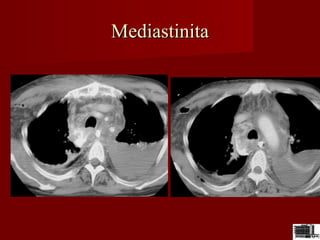

MediastinitaMediastinita

Abces mediastinalAbces mediastinal

Abces mediastinal

dupa o perforatie

laringiana ;latero-

traheal colectie

fluida cu bule de gaz